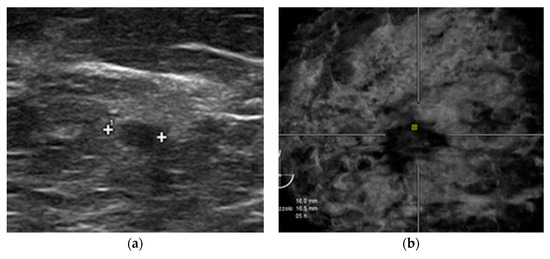

2.2. HHUS Examination

2.3. ABVS Execution

2.4. ABVS Interpretation